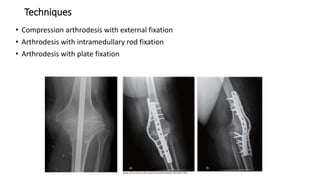

Techniques

• Compression arthrodesis with external fixation

• Arthrodesis with intramedullary rod fixation

• Arthrodesis with plate fixation

Arthrodesis Of Knee •Most frequent indication for knee arthrodesis is failed total knee arthrodesis, secondary to infection • Salvage procedure after failed TKA, expected to have some inferior results compared with primary knee arthrodesis including Lower fusion rates Higher infection rates Shortening of leg

• 61.

Techniques • Compression arthrodesiswith external fixation • Arthrodesis with intramedullary rod fixation • Arthrodesis with plate fixation